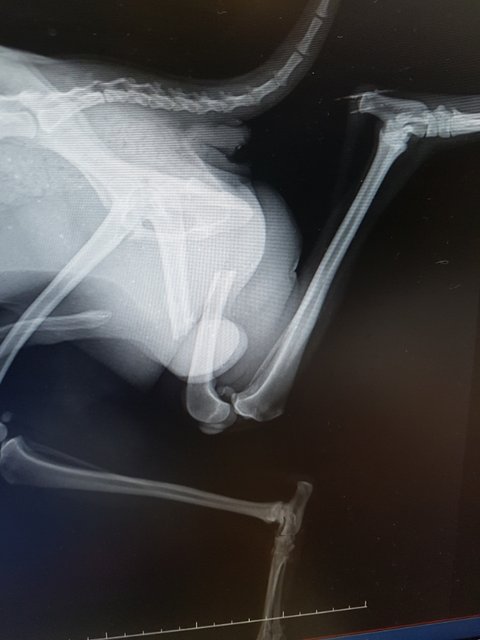

엑스레이 결과 대퇴부가 골절되었습니다.

불행중 다행인지 다른곳 골절은 보이지 않는다고 합니다